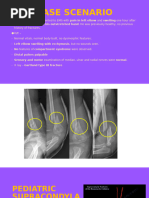

Supracondylar Fracture of the Humerus (SCH)

• Most common elbow fracture

seen in children

• Peak age range: 5-6 years

• Can occur in adults – high

velocity injuries

SCH – 2 types

Depending on the direction of displacement of the distal fragment

Flexion type Extension type

<5% >95%